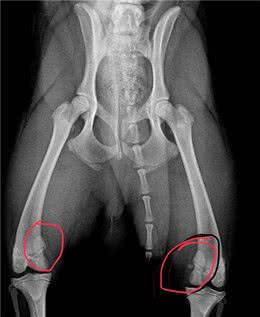

狗狗走路跛脚?多是膝关节异位,介绍自查狗狗膝关节异位方法

膝关节异位处置膝关节1-2级异位症无需手术治疗,可通过药物和物理治疗加以控制。主人可以限制狗跳跃、骑或站立。狗在剧烈奔跑时应该少做一些动作,因为这些动作会使狗的膝盖非常硬,增加狗膝盖的负担。此外,一些止痛药也可以缓解狗的疼痛。3~4级已经属...

有些轻度髋关节发育不良可用药物治疗,而重度髋关节发育不良则需要手术治疗。对于patez病,手术是切除坏死股骨头的唯一治疗方法。膝盖骨脱位可以手术治疗,但它是遗传性髋关节发育不良。对于成年犬来说,十字韧带撕裂通常是因为太重造成的,但一些品种的...